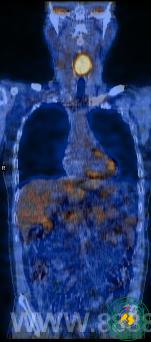

病例3:淋巴瘤放化疗几个疗程后,PET/CT发现腹部残留病灶

PET/CT作为生物分子影像,一问世就给医疗影像诊断世界带来了革新,特别在肿瘤疾病方面获得了重大价值,其价值体现在临床医生对其充分的认识和应用。我院PET/CT投入近一年来,诊断多起疑难病例,为临床提供了重要诊疗信息,现就部分病例汇报,以供交流:病例1为颈部淋巴结肿大患者,外院病检为淋巴结转移鳞癌,外院三甲医院头颈部CT未见原发灶,胸片未见异常,我院PET/CT发现喉咽部高葡萄糖代谢灶,诊断恶性病变。回顾看外院CT片,发现喉咽后壁已明显增厚,只是增强不明显而漏诊,后我院MRI进一步显示为恶性肿瘤。病例2为发现脑部转移灶,常规胸片及其他部位未见原发灶,PET/CT见右肺门局限性高葡萄糖代谢灶,临近气管受压,诊断肺Ca,进一步诊断性CT印证了PET/CT的发现,肺门结构复杂,肿块不大时易漏诊。病例3为淋巴瘤放化疗多个次的患者,患者无不适症状,颈胸部检查正常,PET/CT意外发现腹主动脉旁淋巴结异常高代谢,诊断淋巴瘤(未痊愈),为临床进一步治疗提供依据。